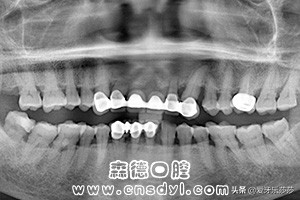

首先呢,是烤瓷冠的数量~

大家都知道,烤瓷冠大都无法过多受力,而当口腔内烤瓷冠的数量较多时,是会影响正常矫正的加力。若只有一两颗烤瓷冠,是可以通过主治医师的检查评估后确定。但当你的牙齿过于拥挤需要拔牙时候,主治医师会在给你设计矫正方案时优先考虑拔除烤瓷冠的。